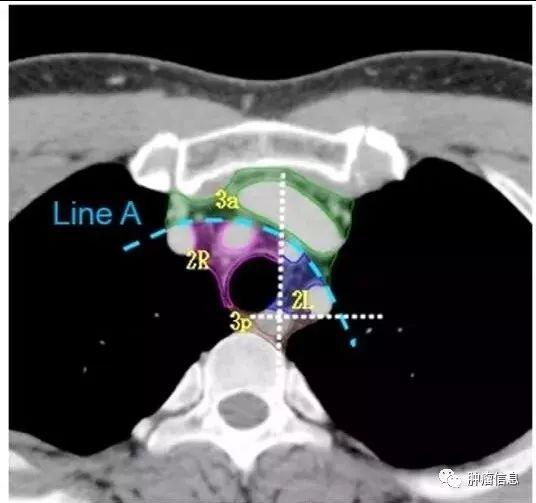

第2组淋巴结

2R:右侧上气管旁,自胸骨柄上界至无名静脉足侧与气管交汇处,自气管右侧至气管左侧缘。2L:左侧上气管旁,自胸骨柄上缘至主动脉弓上缘,气管左侧缘以左。气管左侧缘是2R和2L的分界线。

第3组淋巴结

第3组淋巴结分为3a和3p:3a:前部的血管前淋巴结上界:胸膜顶下界:隆突水平前界:胸骨后后界:上腔静脉前缘3p:后部的气管后淋巴结上界:胸膜顶下界:隆突水平